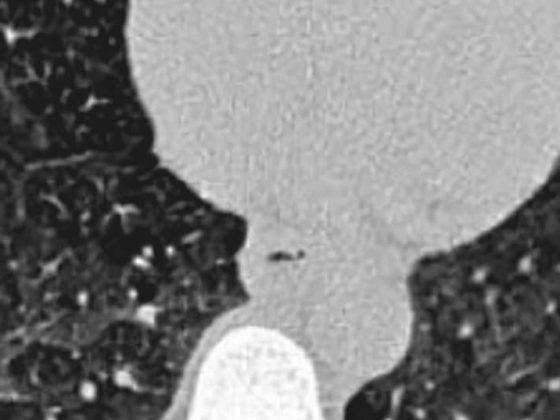

Komplizierte Nierenzysten

• Fortbildung

• Nephrologie

• Onkologie

• Radiologie

• Urologie